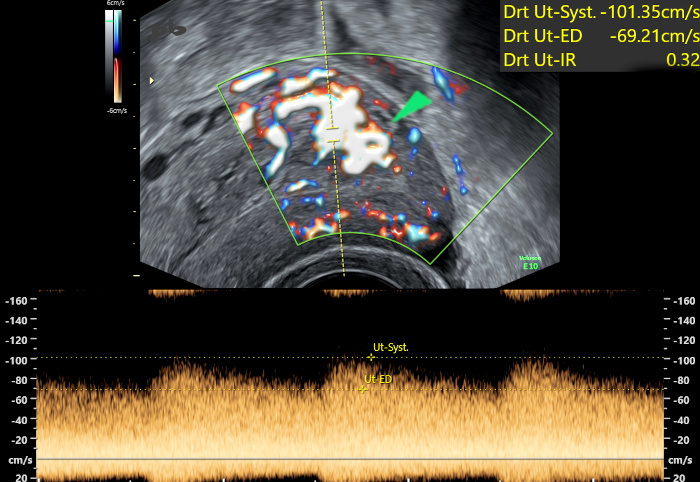

9 – Résidus trophoblastiques

(même patiente que 8)

Echographie doppler – Coupe sagittale.

En postérieur, là où l’interface a disparu, présence de flux nombreux et très rapides (►), dépassant 1m / s. Résistances basses.

Simple surveillance dans les suites. Résolution complète spontanée sur une échographie réalisée 3 mois plus tard.